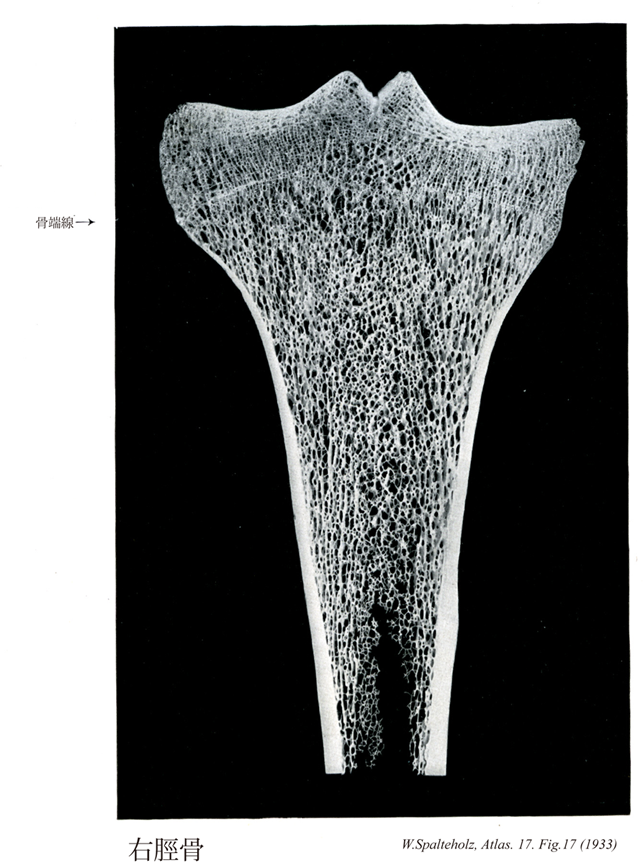

017